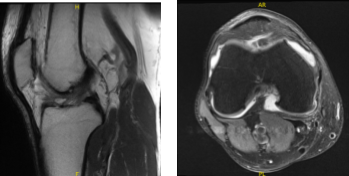

The patient presented MRI results for his left and right knees. For the right, moderate medial compartment arthrosis and a small horizontal tear along the superior articular surface of the posterior horn medial meniscus. There is evidence of previous partial medial meniscectomy.

There is mild lateral and patellofemoral arthrosis. There is a large joint effusion. For the left, Moderate-severe medial knee osteoarthritis with broad full-thickness cartilage loss and bone-on-bone apposition. Complex degeneration and tearing of the medial meniscus. Joint effusion with synovitis/debris.

MRI-3T Right knee non-contrast